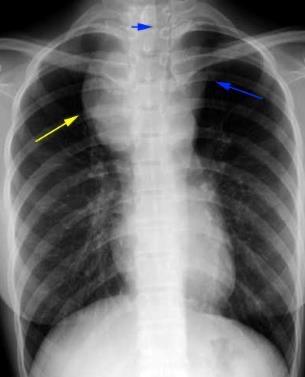

Adultos jóvenes Síndrome de VCS, Compresión de tráquea, etc.

Idiopática. Se asocia a tiroiditis de Riedel, Fibrosis retroperitoneal. AR y enf. autoinmune.

Metisergida Localizada 82%.

Lentamente progresiva